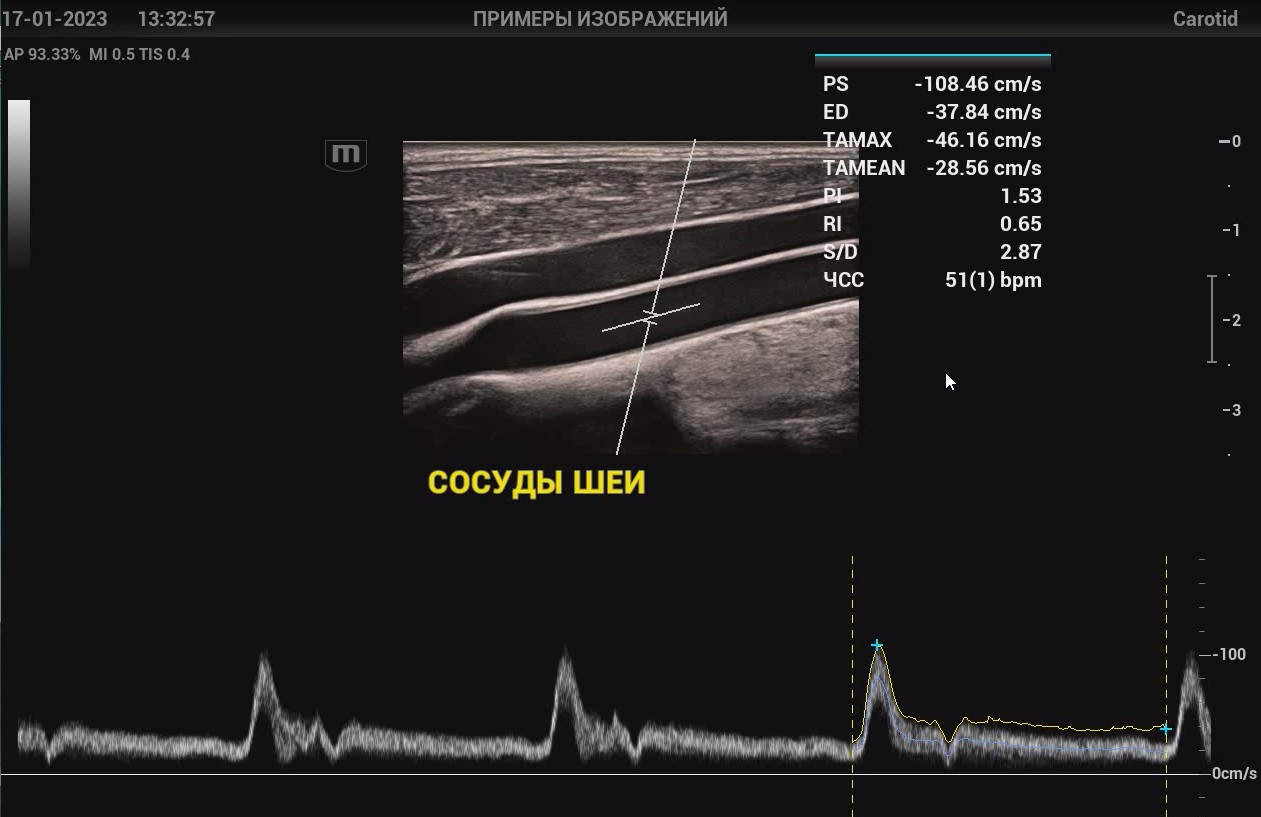

SmartTrack SmartTrack - это технология для сосудистых исследований от Mindray, которая позволяет сократить повторяющиеся и отнимающие много времени шаги во время исследования. Функция автоматически позиционирует допплеровскую рамку и изменяет угол ее наклона в режиме ЦДК, определяет положение и размер контрольного объема в режиме PW.

Auto IMT Автоматическая детекция и вычисление толщины комплекса интима-медиа сонной артерии. Опция Auto IMT позволяет получить точную и эффективную оценку состояния стенки сонной артерии.

V-Flow В технологии V-Flow используются цветные вектора для кодирования скорости и направления движения клеток крови. Благодаря ультравысокой частоте кадров, обеспечивается чрезвычайно показательная, точная и не зависящая от угла визуализация сложных сосудистых гемодинамических показателей.